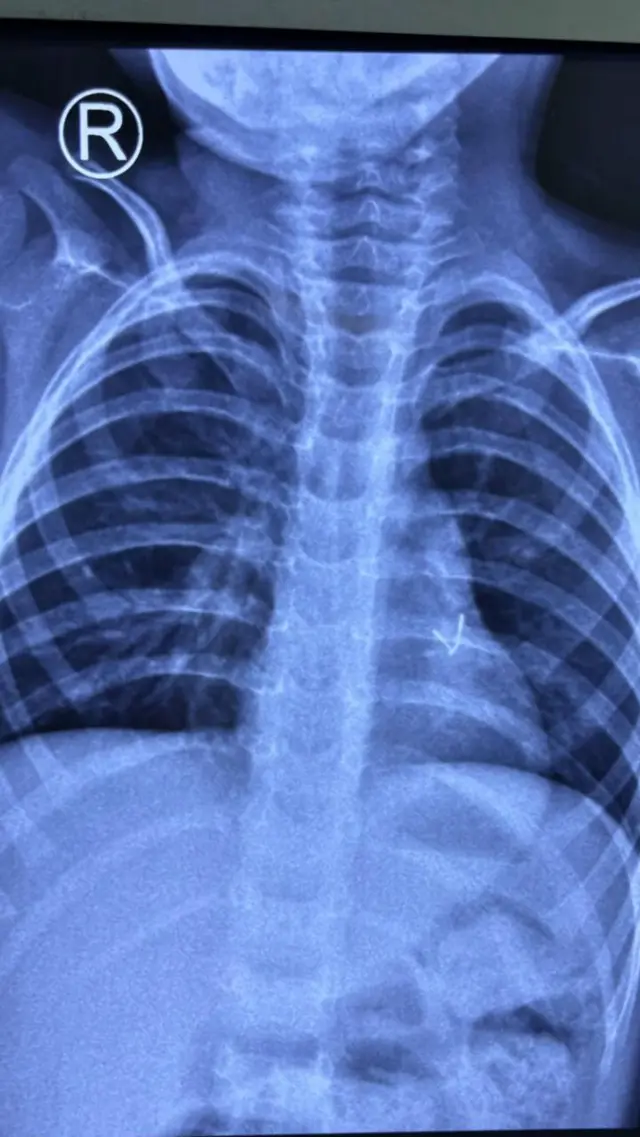

एका दुर्मिळ व असाधारण वैद्यकीय केसमध्ये जसलोक हॉस्पिटल अँड रिसर्च सेंटरमधील डॉक्टरांनी साडेतीन वर्षांच्या मुलाच्या फुफ्फुसात अडकलेला धातूचा एलईडी बल्ब यशस्वीरीत्या काढला.

यामुळे तीन महिन्यांपासून त्याला सतत खोकला आणि श्वसनाचा होत असलेला त्रास अखेर दूर झाला. राहुल (गोपनीयतेसाठी नाव बदलले आहे) सुरुवातीला निदान झालेल्या न्यूमोनिया आजाराने ग्रस्त होता आणि अँटीबायोटिक्सचे अनेक औषधोपचार करण्यात आले.

मोठ्या प्रमाणात काळजी घेतल्यानंतर देखील, त्याची लक्षणे कायम राहिली. त्यानंतर त्याची सखोल तपासणी करण्यात आली. यात सीटी स्कॅन करण्यात आले. यामधून त्याच्या डाव्या ब्रोन्कसमध्ये खोलवर धातूचा तुकड्यासारखा भाग असल्याचे आढळून आले.

कोल्हापूरात फ्लेक्सिबल ब्रॉन्कोस्कोपीच्या अयशस्वी प्रयत्नांनंतर या मुलाला जसलोक हॉस्पिटलमध्ये आणण्यात आले, जेथे ब्रॉन्कोस्कोपीमध्ये गिळण्यात आलेला एलईडी बल्ब ब्रोन्कस मध्ये आढळून आला.

त्यानंतर डॉ. विमेश राजपूत आणि डॉ. दिव्य प्रभात यांनी मिनी थोरॅकोटॉमी (4सेमी कट) केली, ज्यामुळे खेळण्यांच्या गाडीतून गिळलेला एलईडी बल्ब यशस्वीरित्या काढून टाकण्यात आला आणि मुलाच्या फुफ्फुसांचे कार्य पूर्ववत करण्यात आले. ॲनेस्थेसियोलॉजी सल्लागार डॉ. अनुराग जैन यांनीही या शस्त्रक्रियेत भाग घेतला.

याबाबत बोलताना जसलोक हॉस्पिटलमधील थोरॅसिस सर्जन डॉ. विमेश राजपूत म्हणाले, "आम्ही ऑपरेट केलेली ही सर्वात दुर्मिळ केस होती. एलईडी बल्ब फुफ्फुसामध्ये खोलवर गेला होता आणि समकालीन उपचार पद्धती तो बल्ब बाहेर काढण्यामध्ये अयशस्वी ठरल्या. काळजीपूर्वक नियोजन केलेल्या मिनी थोरॅकोटॉमीसह आम्ही सुरक्षितपणे एलईडी बल्ब बाहेर काढला आणि मुलाला जीवनदान मिळाले.''